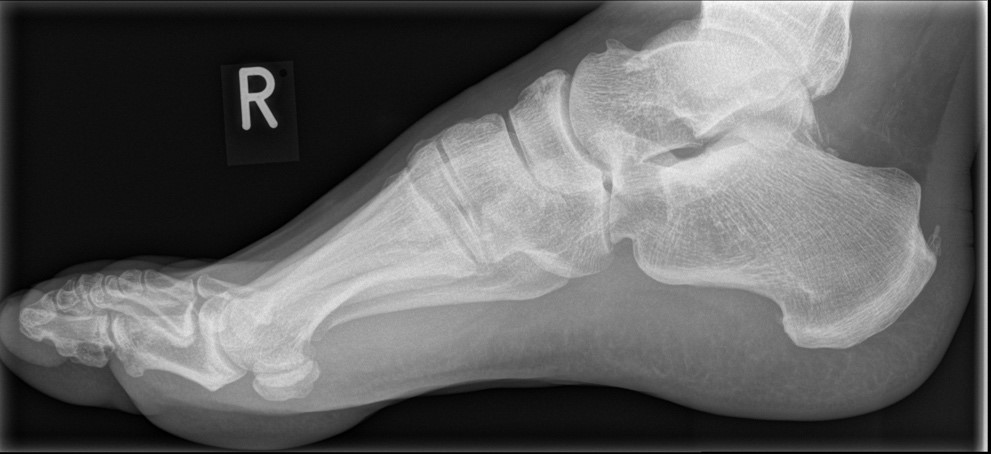

Abbildung 1: Plantarer und dorsaler Sporn im Röntgenbild und im MRT

Abb. 1a und Abb. 1b: großer dorsaler Fersensporn und ein minimaler plantarer Sporn, Patient, 50 Jahre.

Abb. 1c: Bild eines isolierten großen plantaren Fersensporns. Patientin, 32 Jahre.

Zum Lesen der Bildbeschreibung und zur Vollansicht bitte die Bilder anklicken. Bilder: Manfred Thomas.